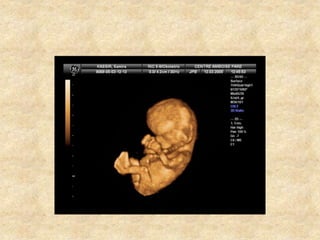

• Mode 3D permet balayage automatique ,

acquisition de volume d’échos dont le

traitement informatique dans tous les plans

de coupe .